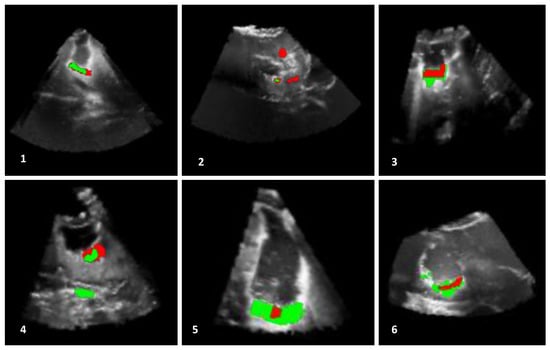

The outcomes, obtained by the automatic proposed method, are presented in Figure 7, Figure 8 and Figure 9. In addition, the algorithm results (in green) and the ground truths (in red) are overlaid on a selected slice of the 3D iB-mode images for visualization purposes. Table 2 summarizes the qualitative and quantitative evaluation. The former is based on expert observations, and the latter is performed by using the overlap, accuracy, area under the curve and error rate measures. The experiments showed that our approach succeeded in detecting the position of all tumor remnant areas in 15 out of 19 patients (). For these cases, a qualitative coding of 1/−1 (all tumorous regions were detected) or 1/1 (all tumorous regions were detected and extra suspected regions, as well) was observed. Regarding the four unsuccessful cases, the areas with tumorous tissue were partially detected in two patients (Patients 2 and 7, where ), and the algorithm failed in the two other cases (Patients 14 and 18, where ). One failure reason is the position of tumor residuals near the image top (Patients 7 and 18). These areas are removed in the preprocessing steps to eliminate artifacts caused by the US probe. The method was also tested on patient data from the set B where false positives were detected in the cases of Patients 20 and 23 and none for Patients 21 and 22.

Figure 7.

Results of residual tumor identification from Patients 1 to 6. The results obtained with the proposed automatic method (in green) and in the manual segmentation (in red) are overlaid on a selected slice of the 3D iB-mode image data. The algorithm missed tumorous structures in Patient 2 and identified extra regions in Patient 4.